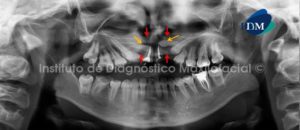

Paciente masculino de 15 años de edad que es referido por presentar alteración morfológica de las estructuras blandas y duras del sector anterior de los maxilares superiores. A la evaluación de la radiografía panorámica se observan defectos óseos (uno a cada lado distal de los incisivos centrales) que se extienden desde la cima del reborde alveolar hasta el piso de fosa nasal, comprometiendo este último (flechas rojas). Así mismo, se evidencia que los defectos óseos se encuentran asociados a la ausencia de las piezas 12 y 22; así como, a la presencia de dos piezas supernumerarias (flechas amarillas). Signos radiográficos compatibles con Paladar Fisurado Bilateral (Fig. 1).